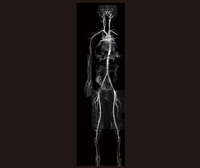

非造影MRAは,さまざまな工夫をすることによって,ほぼ全身が評価できると考えられる(図4)。

図4

図4 非造影 MRA